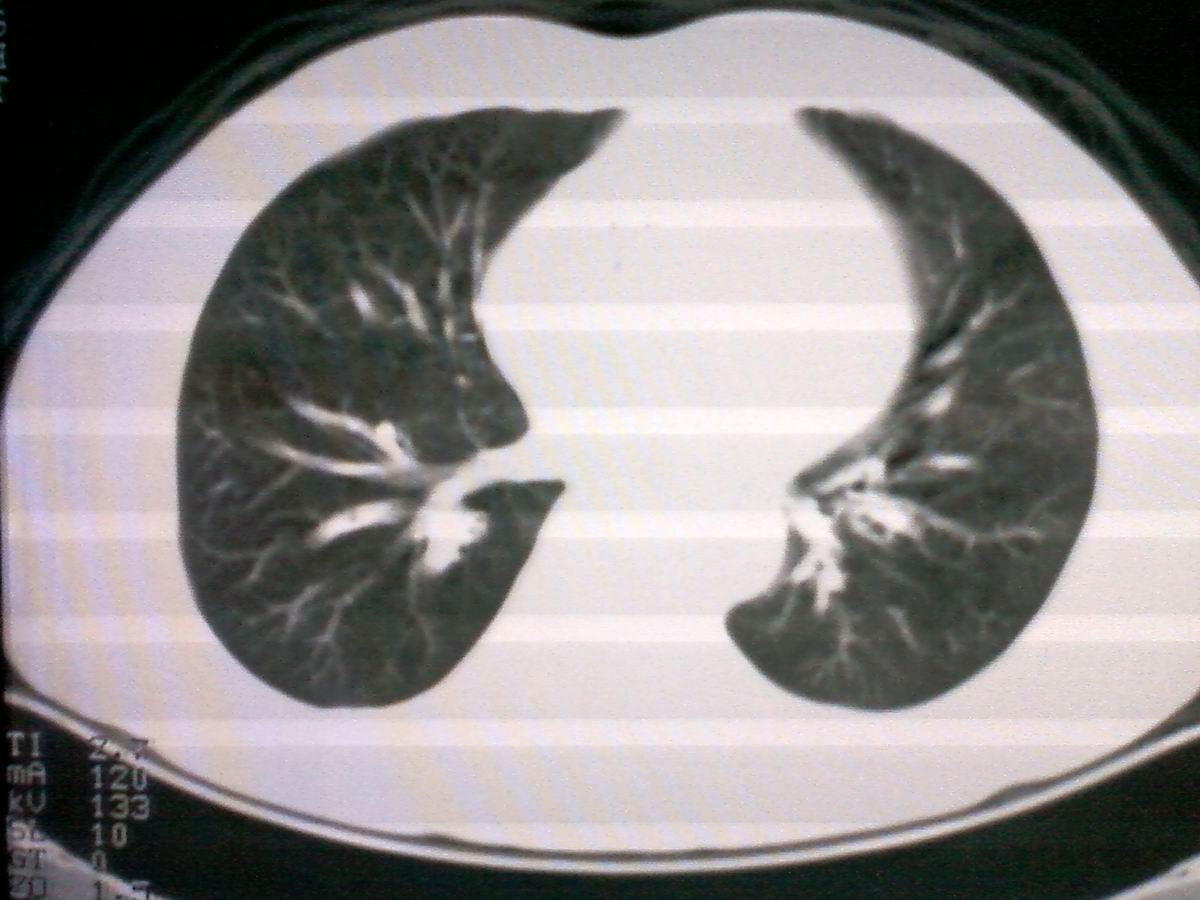

标题: CT25801:患者男性,65岁,临床提示双肺可闻及广泛罗音,看 [打印本页]

标题: CT25801:患者男性,65岁,临床提示双肺可闻及广泛罗音,看

气管后部见半圆形软组织密度病灶,考虑占位,建议气管镜除外鳞癌。

气管上段的肿瘤多为良性乳头状瘤,气管下段的肿瘤多为鳞癌,气管中段的良恶性各占一半。本例位于气管下段,先按恶性处理。不过纤支镜是免不了的。

进修时见过一例类似的并例,不过肿块位置较高,在胸锁关节以上的气管内,如果不是扫描得高,几乎忽略掉。后来支气管镜检为鳞癌。